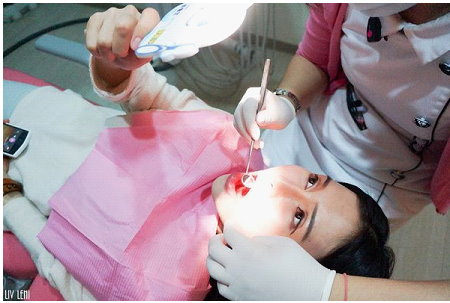

你們看~這是我牙周治療前的口腔狀況,

在診所的診療用強光下才發現我有幾顆牙的牙齦邊緣,

已 經 出 現 牙 結 石 了!

牙肉也稍微的紅腫,這程度真是我察覺不到的!!!!

(什麼!!?

竟然還有流血!!!)

所以牙周病被稱隱形殺手根本沒有誇張!

時間再久一些,我真的會成為牙周病患者了耶~~~